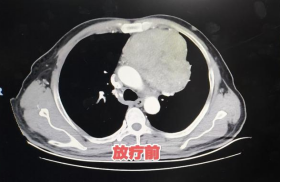

治疗全程患者无不良反应,与常规放疗相比,患者放疗疗程缩短一半,耐受性良好。放疗结束3周后复查显示,患者前纵隔占位显著减退,为后续治疗创造有利条件。

患者放疗前后肿瘤变化对比